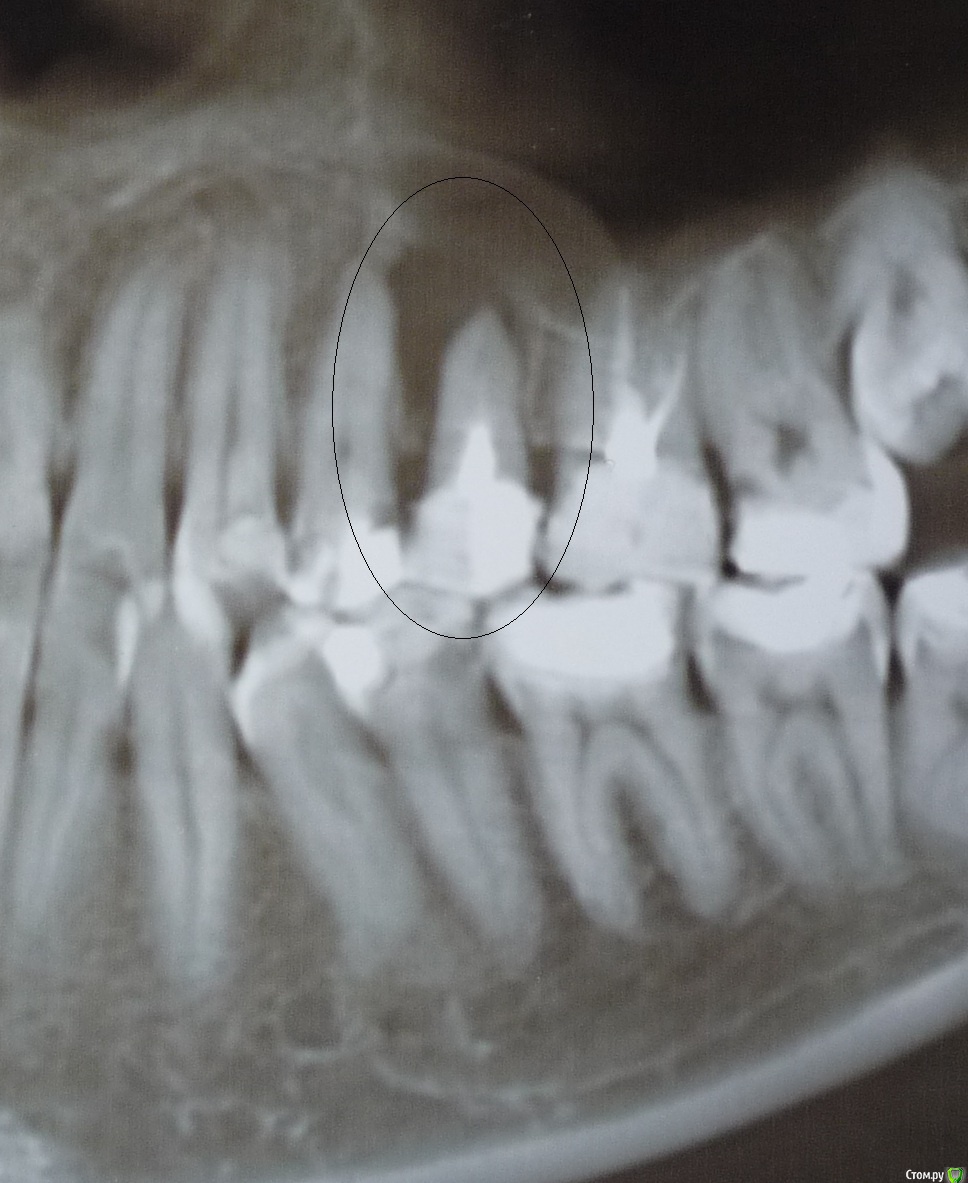

12345k Опубликовано 23 августа, 2019 Поделиться Опубликовано 23 августа, 2019 Здравствуйте!Подскажите, пожалуйста, как лучше поступить с зубами 25, 46, 47? Воспаление обнаружилось год назад на рентгеновском снимке. У зубов имеются свищи. Спасибо. Ссылка на комментарий

St. Опубликовано 2 сентября, 2019 Поделиться Опубликовано 2 сентября, 2019 Добрый день.Если еще актуально. Корневые каналы можно перелечить. Шансы на успех достаточно высокие .Могут возникнуть вопросы с 47 по этому снимку не понятно, но там может быть перфорация или трещина. Ссылка на комментарий

12345k Опубликовано 31 января, 2020 Автор Поделиться Опубликовано 31 января, 2020 В продолжение моей темы. Мне перелечили зуб 25: распломбировали, промыли каналы, закладывали кальсепт с йодоформом на 2 недели, затем запломбировали каналы на постоянной основе. В процессе несколько раз делали снимки (они не на руках). Снимок до лечения выложен ранее.Хотела бы задать вопрос уважаемым докторам форума. Может, кто-нибудь ответит? К своему доктору пока нет возможности попасть.До перелечивания на десне рядом с зубом 25 был свищ, из которого самостоятельно отделялось содержимое. После промывания каналов и кальция прекратились выделения из свища, но на десне был виден небольшой круглый шрам. Спустя месяц после пломбировки каналов снова начались периодические скудные выделения из свища белого цвета.Означает ли это, что инфекция не устранена или находилась не в каналах зуба? Насколько неблагоприятен прогноз? Насчет резекции доктор сразу сказал, что этот способ на подойдет.Спасибо всем, кто откликнется. Ссылка на комментарий